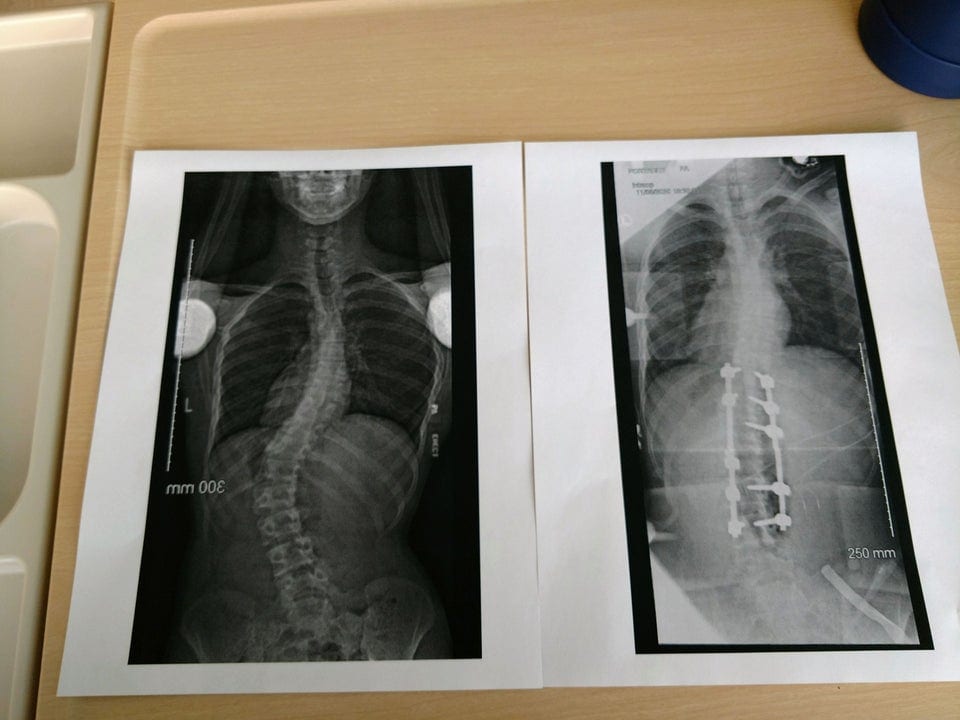

“Спина мого брата до і після операції з виправлення сколіозу”